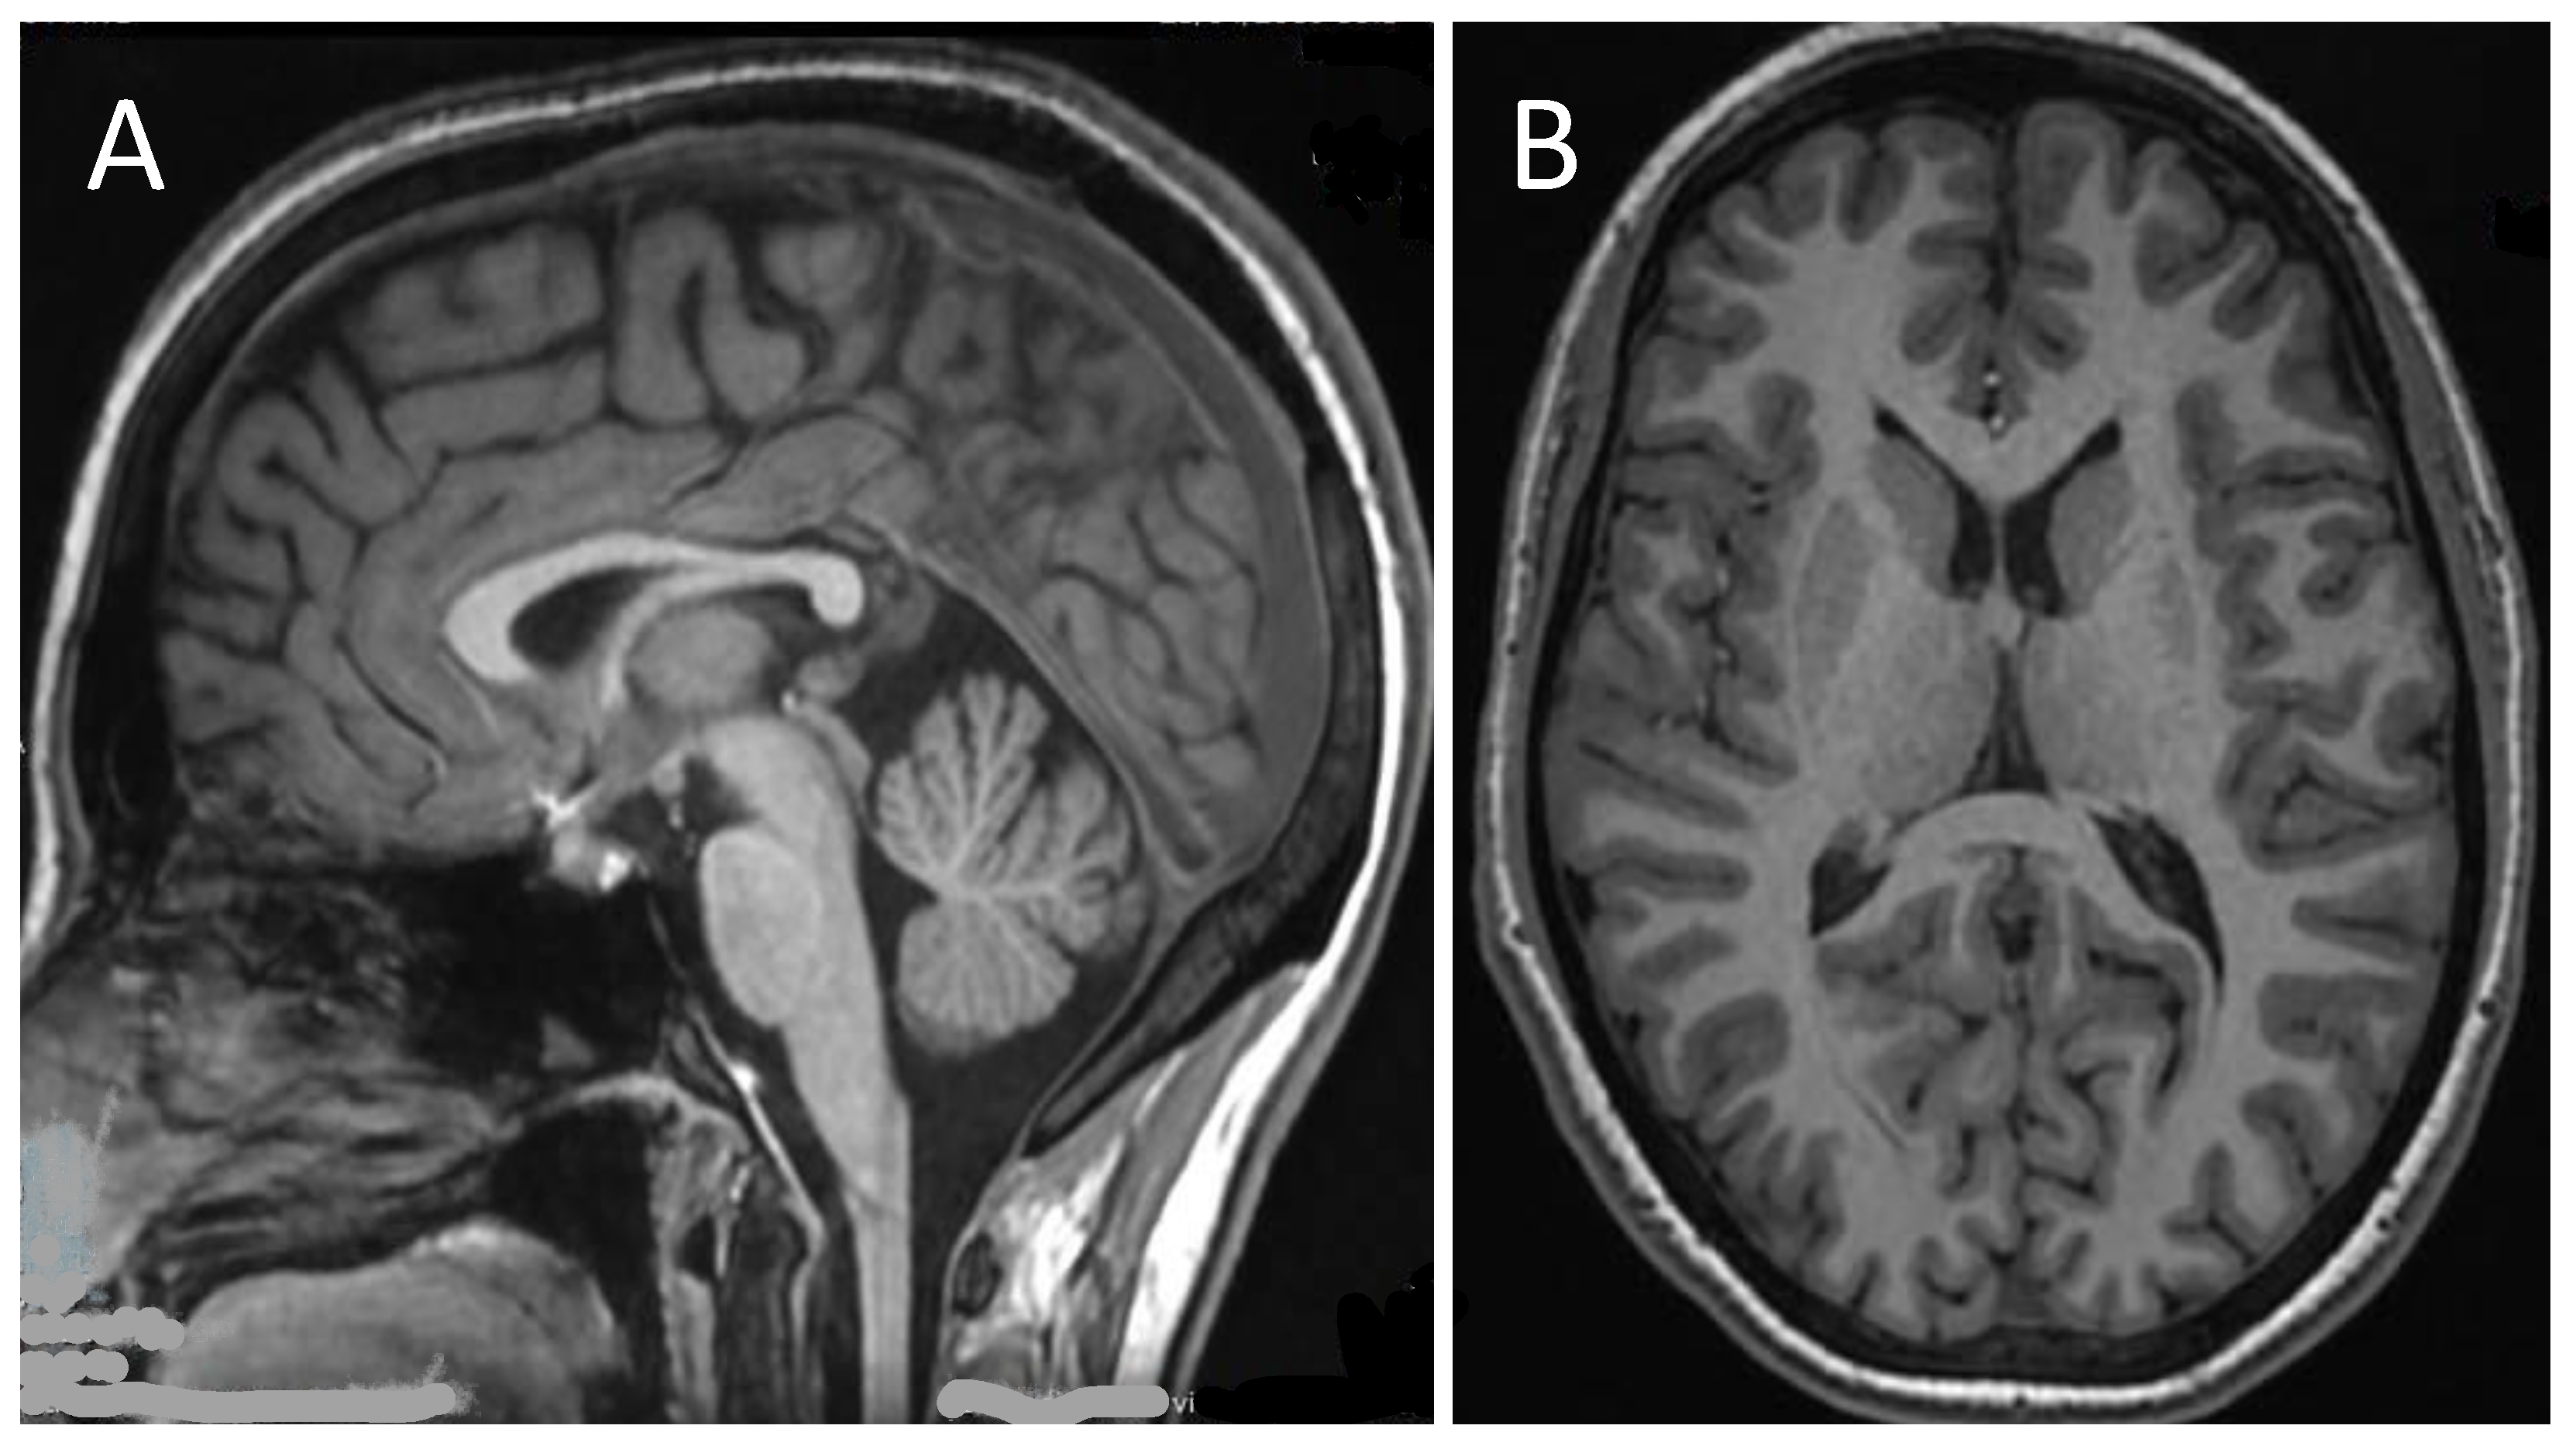

2. Case Presentation